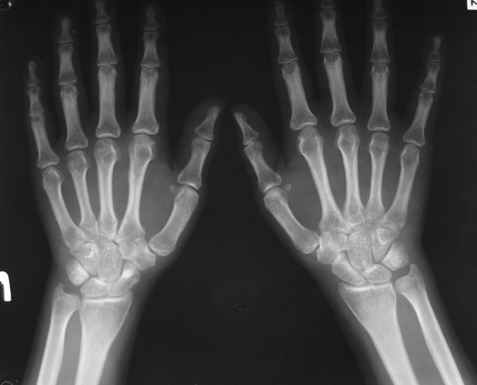

Уважаемые коллеги! Вопрос по уточнению диагноза. Методы дополнительной диагностики? Ваше мнение по данному случаю? Спасибо!

Женщина, 30 лет.

Жалобы на сильные боли в суставах и мышцах (без четкой локализации), припухлость суставов, повышение температуры 38-39 гр.

Считает себя больной с 1994 г., когда появились боли в легких. В 1996 г. - боли в спине без четкой локализации. 2002 г. - роды, через 10 мес. сильные мышечные боли. 2004 г. - плеврит и увеит (сейчас - миопия, -1,-1,5, астигматизм). Периодические увеличения лимфатических узлов (чаще шейных), симптомы васкулита.

Диагноз: Ревматоидный артрит неизвестной этиологии (реактивный урогенитальный артрит или полиартрит?)